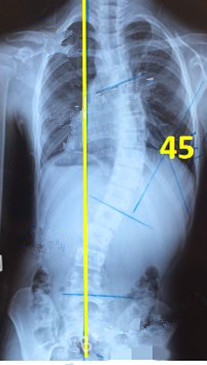

脊柱側(cè)彎患者的支具矯正

脊柱側(cè)彎矯形器(支具)是通過外力對側(cè)彎的脊柱進(jìn)行矯正。所以,支具的力點(diǎn)位置及大小非常重要。當(dāng)患者生長發(fā)育速度較快或支具矯正效果較好時(shí),側(cè)彎矯正的進(jìn)程也會較快,此時(shí)為了充分利用孩子生長階段的最佳矯正期,一定要對支具進(jìn)行及時(shí)的調(diào)整和更換。

一般經(jīng)過三個月至六個月的治療,對稱度都能得到改善,力線回正。

未穿支具